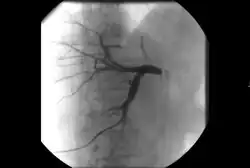

• Angiography: Imaging the blood vessels to look for abnormalities with the use of various contrast media, including iodinated contrast, gadolinium based agents, and CO2 gas.[3]

1. Angiography: Sometimes referred to as traditional angiography, catheter angiography or digital subtraction angiography (DSA). A small needle is inserted into a blood vessel, then exchanged for a catheter over a wire. The catheter is directed at the vessel to be studied, and contrast is directly injected to evaluate the lumen under video X-ray. This is an older technique than modern CT angiography or MR angiography, but provides unique advantages. With a catheter in place, provocative maneuvers can be performed such as breath holds or instillation of vasodilators, to evaluate a patient's blood flow dynamically. This can reproduce symptoms and identify functional abnormalities in a vessel that a static CT or MR imaging cannot.[80][81] Angiography provides the basis for all endovascular therapy.